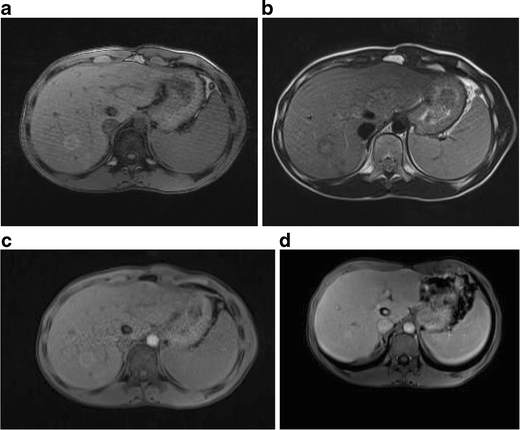

Ultrasound, CT scans, and MRI are the first steps to detect and study the size, location, and nature of the lesion.

Blood tests, including liver function tests and markers like AFP (Alpha-Fetoprotein), help in assessing cancer risk.

In some cases, a needle biopsy is done to examine the tissue under a microscope and confirm the type of lesion.

For complex or unclear cases, PET scans and contrast-enhanced imaging help in detecting cancer spread or staging.